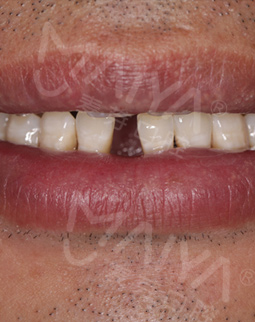

我是个私企老板,今年39岁。前几年由于一些意外,使我的前牙掉了,特别影响形象,很多都问我这年纪轻轻牙咋就掉了......后来做了活动假牙,但是清洁特别不方便,还感觉挺难受的。

今年回老家,假牙坏了,咨询了本地医院,他们说做不了,后来听说这家机构技术不错,了解到这里硕博专家不仅种植经验丰富,还经常到世界各地交流种牙技术,经过几家机构的对比,最终选择了这里。据工作人员说,他们即将举办种牙手术直播活动,报名之后还有种牙优惠,我决定尝试一下。